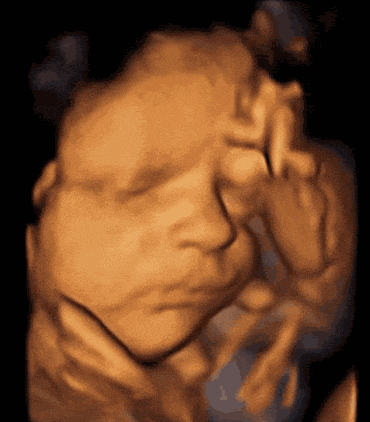

孕妈咪们都知道

孕中期有项不可缺少的排畸

四维彩超检查

不仅能立体显示胎儿器官发育情况

甚至观察到胎儿在母体里的状态

四维彩超还能通过实时立体成像

看到胎儿的形态及面部表情

还有宝宝在子宫内的一举一动